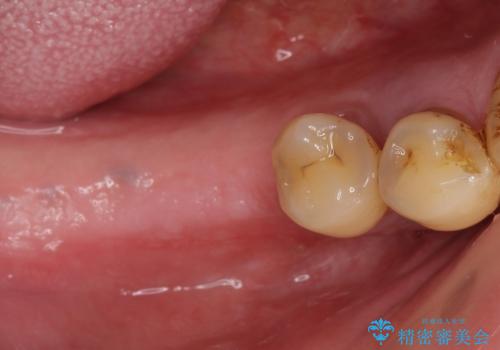

- 歯がないまま放置しており咬めないことを主訴に来院された患者様です。

仕事が忙しくなかなか自分のことに気が回らなかったそうですが、どんどん歯が抜け落ちて「もう限界だ!」と思い受診を決断したとのことでした。

精査したところ、全顎的な重度の歯周病により右下の小臼歯(右下4)激しい動揺を認めました。